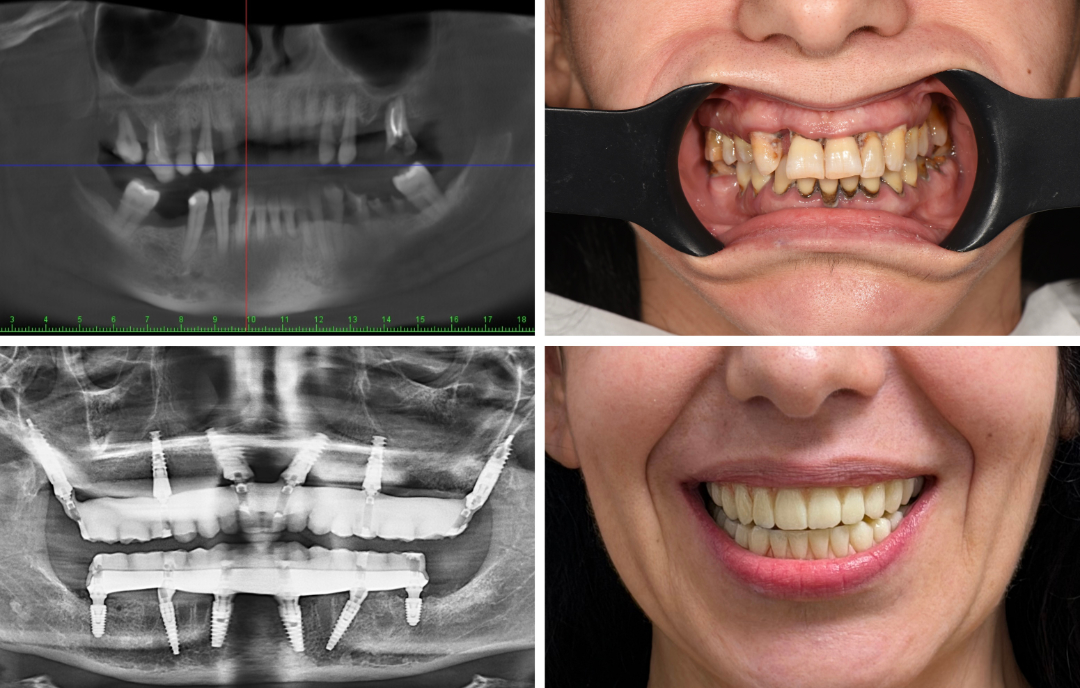

Ausgangssituation

Eine 40-jährige Patientin mit ausgeprägter Zahnarztphobie und desolatem Zahnstatus suchte nach der Möglichkeit einer Behandlung in Vollnarkose. Sie wünschte sich eine allumfassende operative Lösung.Der 42-jährige Patient hatte seine Zahngesundheit infolge ausgeprägter Zahnarztangst über längere Zeit vernachlässigt. Im Oberkiefer waren alle noch vorhandenen Zähne nicht mehr erhaltungswürdig. Aufgrund der fortgeschrittenen Entzündungsprozesse hatte sich der Alveolarknochen vollständig zurückgebildet, sodass nur spezielle Implantatsysteme in Betracht gezogen werden konnten.All-on-4/All-on-6 ermöglicht ohne Augmentationen die Versorgung des vollständigen Zahnbogens auf nur vier Implantaten innerhalb weniger Stunden. Noch am Behandlungstag erhalten Sie einen festsitzenden und sofort belastbaren provisorischen Zahnersatz.

Lösung

In ITN: Navigierte Rekonstruktion des Oberkiefers mit herkömmlichen Implantaten und Pterygoid-Implantaten sowie sofortiger provisorischer Brücke.

Vorteile

Die junge Angstpatientin erhielt die gewünschte Implantatlösung – in kürzester Zeit und unter Vollnarkose.Gerade für Angstpatienten stellt die navigierte Full-Arch-Rekonstruktion eine vielversprechende Option dar: Sie ermöglicht nicht nur eine präzise und schonende Therapie mit festsitzendem Zahnersatz in Vollnarkose, sondern auch eine Rückkehr zu mehr Lebensqualität – oft schon unmittelbar nach dem Eingriff.